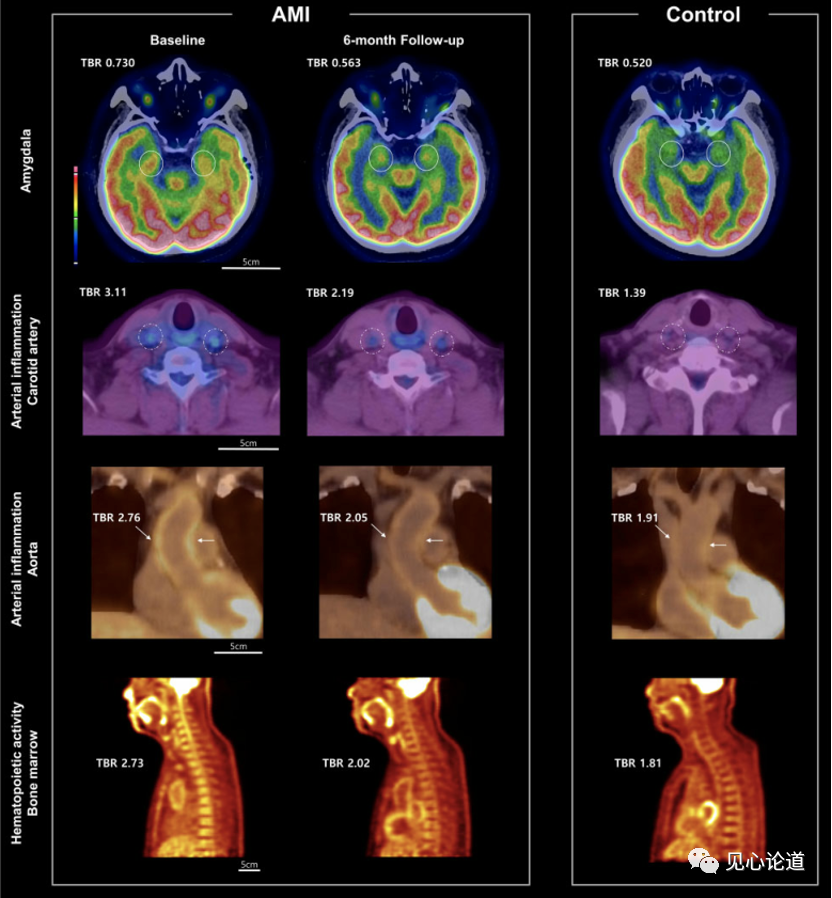

本研究共入组62例患者(45例AMI,平均60.0岁,男性占84.4%;对照组17例,平均59.6岁,男性占76.4%)。10例急性心肌梗死患者在6个月后进行系列18F-FDG正电子发射断层扫描,以评估随时间的变化。

图2:扫描图像呈现杏仁核、颈动脉、主动脉和骨髓的18F-FDG摄取模式示例